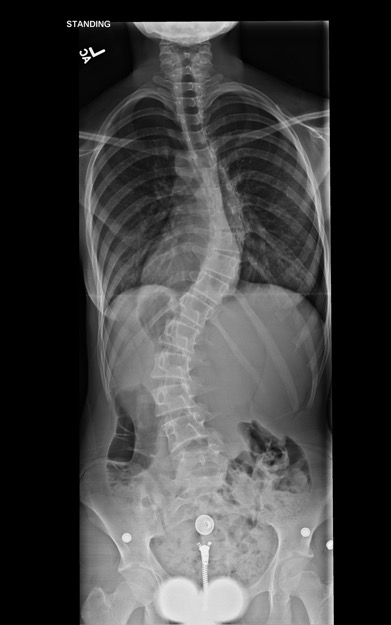

Diagnostic tests. The initial radiograph of the spine showed a right-sided thoracic curve and a left-sided lumbar curve measuring 46° and 51°, respectively (Figure 3). Repeated imaging 4 months later showed progression to 56° and 57°, respectively. A genetic consult ruled out Marfan syndrome (Ghent score, 1) and Ehlers-Danlos syndrome (Beighton hypermobility score, 3). No mitral valve prolapse or aortic root dilation were noted on the echocardiogram. The patient received a diagnosis of adolescent idiopathic scoliosis and underwent a posterior spinal fusion with instrumentation.

Figure 3. Posteroanterior radiograph of the spine.